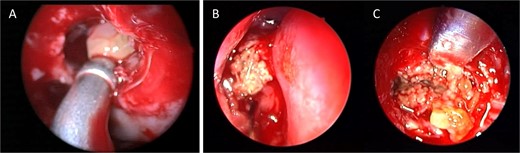

Intra-operative endoscopic view showing (A) polyps in the left osteomeatal complex with (B and C) fungal mud and mucin.

Coronal NCCT image of the paranasal sinuses showing isolated left complete heterogenous maxillary sinus opacification with obstructed left osteomeatal complex.

A 37-year-old female with a history of bronchial asthma, complained mainly of chronic headache, left sided facial pain, which was associated with persistent post-nasal drip. Endoscopic examination showed left-sided tenacious discharge filling the middle meatus with grade two polyps. NCCT (Fig. 5) showed left isolated heterogenous maxillary sinus opacity suggestive of allergic fungal sinusitis. She underwent endoscopic sinus surgery (Fig. 6) with removal of fungal mucin and mud, complete left maxillary sinus aeration was ensured. The patient was free of symptoms during her 1 week follow up.